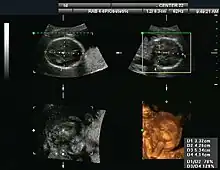

Three-dimensional imaging is done by combining B-mode images, using dedicated rotating or stationary probes. This has also been referred to as C-mode.[4]

Obstetrical sonography was originally developed in the late 1950s and 1960s by Sir Ian Donald[19][20] and is commonly used during pregnancy to check the development and presentation of the fetus. It can be used to identify many conditions that could be potentially harmful to the mother and/or baby possibly remaining undiagnosed or with delayed diagnosis in the absence of sonography. It is currently believed that the risk of delayed diagnosis is greater than the small risk, if any, associated with undergoing an ultrasound scan. However, its use for non-medical purposes such as fetal "keepsake" videos and photos is discouraged.[21]

3-D images can be generated by acquiring a series of adjacent 2-D images. Commonly a specialized probe that mechanically scans a conventional 2-D image transducer is used. However, since the mechanical scanning is slow, it is difficult to make 3D images of moving tissues. Recently, 2-D phased array transducers that can sweep the beam in 3-D have been developed. These can image faster and can even be used to make live 3-D images of a beating heart.